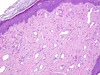

Soft tissue, forearm mass growing over last few weeks, male.

Nodular fasciitis

- Subq mass

- Blue, spindled, cellular mass

- lighter and darker staining areas

- Biphasic:

- Lighter: tissue culture appearance

- Darker: more cellular, spindled

- Extravasated RBCs

- MYH9/USP6

- May become more cellular/less myxoid/less tissue culture-like over time